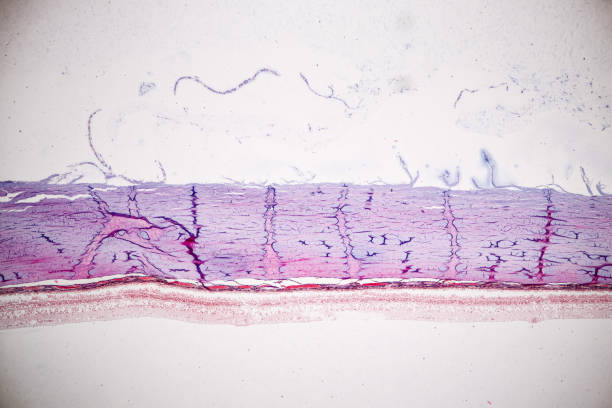

녹내장은 안통과 두통뿐 아니라, 시신경 손상으로 인한 안구 충혈을 유발할 수 있습니다. 만일, 이러한 안구 충혈이 지속해서 발생하는 경우 녹내장을 의심해볼 수 있습니다.